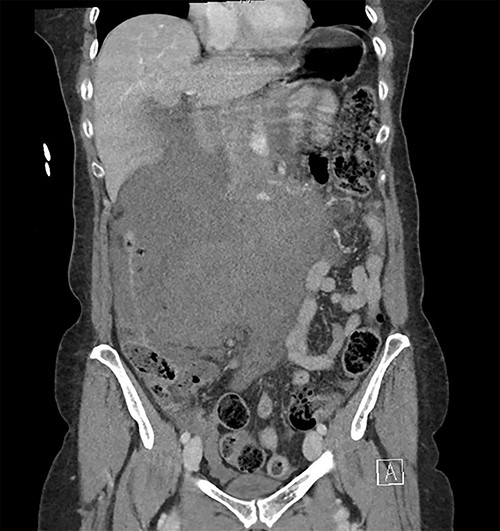

Initially, the main diagnosis considered was an aortic dissection. Other initial general surgical differentials were a perforated viscous or severe pancreatitis. Computed tomography (CT) angiogram showed a 6 mm pseudoaneurysm arising from a branch vessel 3 cm distal to the origin of the SMA. There was no active arterial blush; however, there was a large associated mesenteric haematoma (measuring 4.5 × 8.0 × 13 cm) with large volume haemoperitoneum (Figs 1–3). There was also a splenic artery aneurysm measuring 5 mm with no evidence of active haemorrhage. After the CT scan, she was noted to be haemodynamically unstable when lying supine, due to inferior vena cava compression by the mesenteric haematoma. A pillow was placed under her left lateral side to act as a wedge to reduce this. She proceeded to urgent angioembolization by interventional radiology, which confirmed the pseudoaneurysm on angiography (Fig. 4, left). The SMA was accessed and the aneurysm was successfully embolized with 3 mm diameter 15 cm length Ruby micro-soft detachable coil (Fig. 4, right).

Coronal image of the retroperitoneal haematoma in portal venous phase.